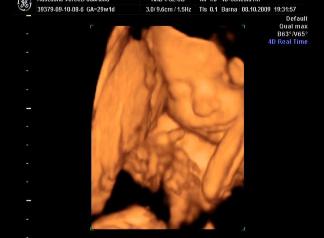

Briell! Nagyon szepek a kepek, a szemtakarosak mindig nagyon cukik, de a labikos sem semmi